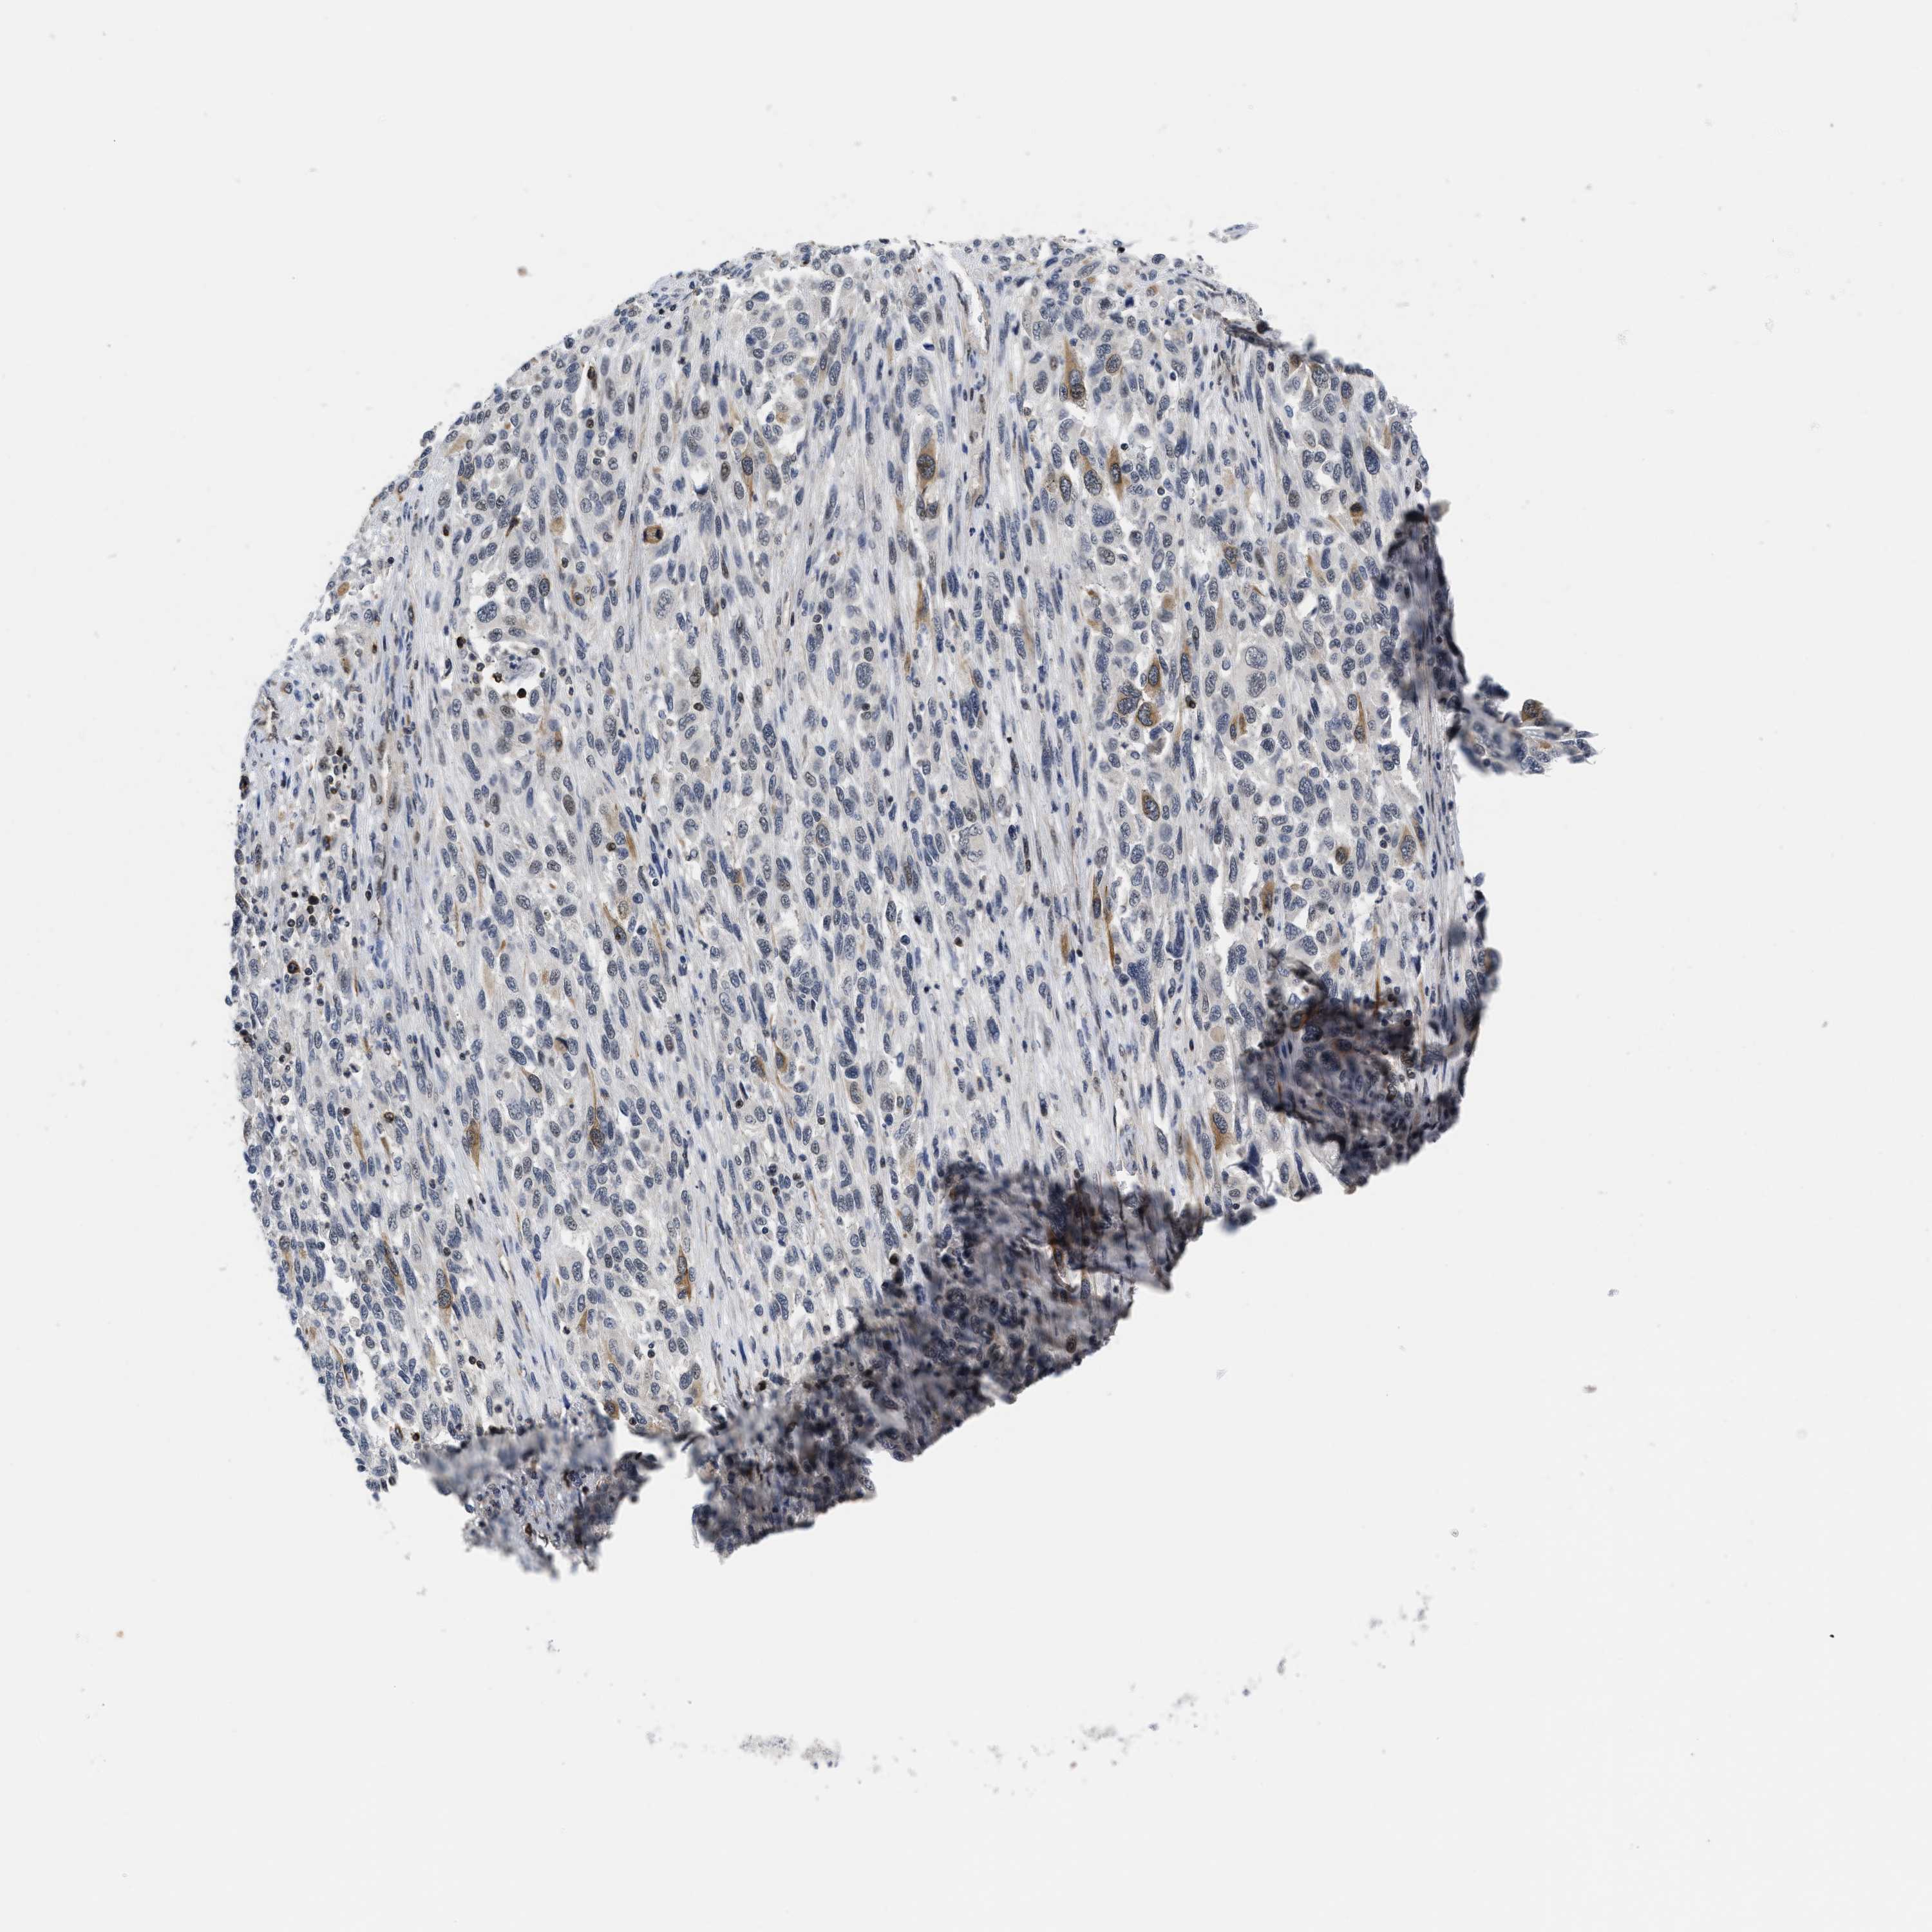

MELANOMA - Protein expressioni

A mouse-over function shows sample information and annotation data. Click on an image to view it in a full screen mode. Samples can be filtered based on level of antibody staining by selecting one or several of the following categories: high, medium, low and not detected. The assay and annotation is described here.

Note that samples used for immunohistochemistry by the Human Protein Atlas do not correspond to samples in the TCGA dataset.

Antibody stainingi

Antibody staining in the annotated cell types in the current human tissue is reported as not detected, low, medium, or high, based on conventional immunohistochemistry profiling in selected tissues. This score is based on the combination of the staining intensity and fraction of stained cells.

Each image is clickable and will lead to virtual microscopy that enables deeper exploration of all samples and also displays staining intensity scores, fraction scores and subcellular localization as well as patient and tissue information for each sample.

Antibody HPA001275

Antibody CAB017442

Staining

High

Medium

Low

Not detected

Intensity

Strong

Moderate

Weak

Negative

Quantity

>75%

75%-25%

<25%

None

Location

Nuclear

Cytoplasmic/membranous

Cytoplasmic/membranous,nuclear

Malignant melanoma, NOS

Malignant melanoma, Metastatic site